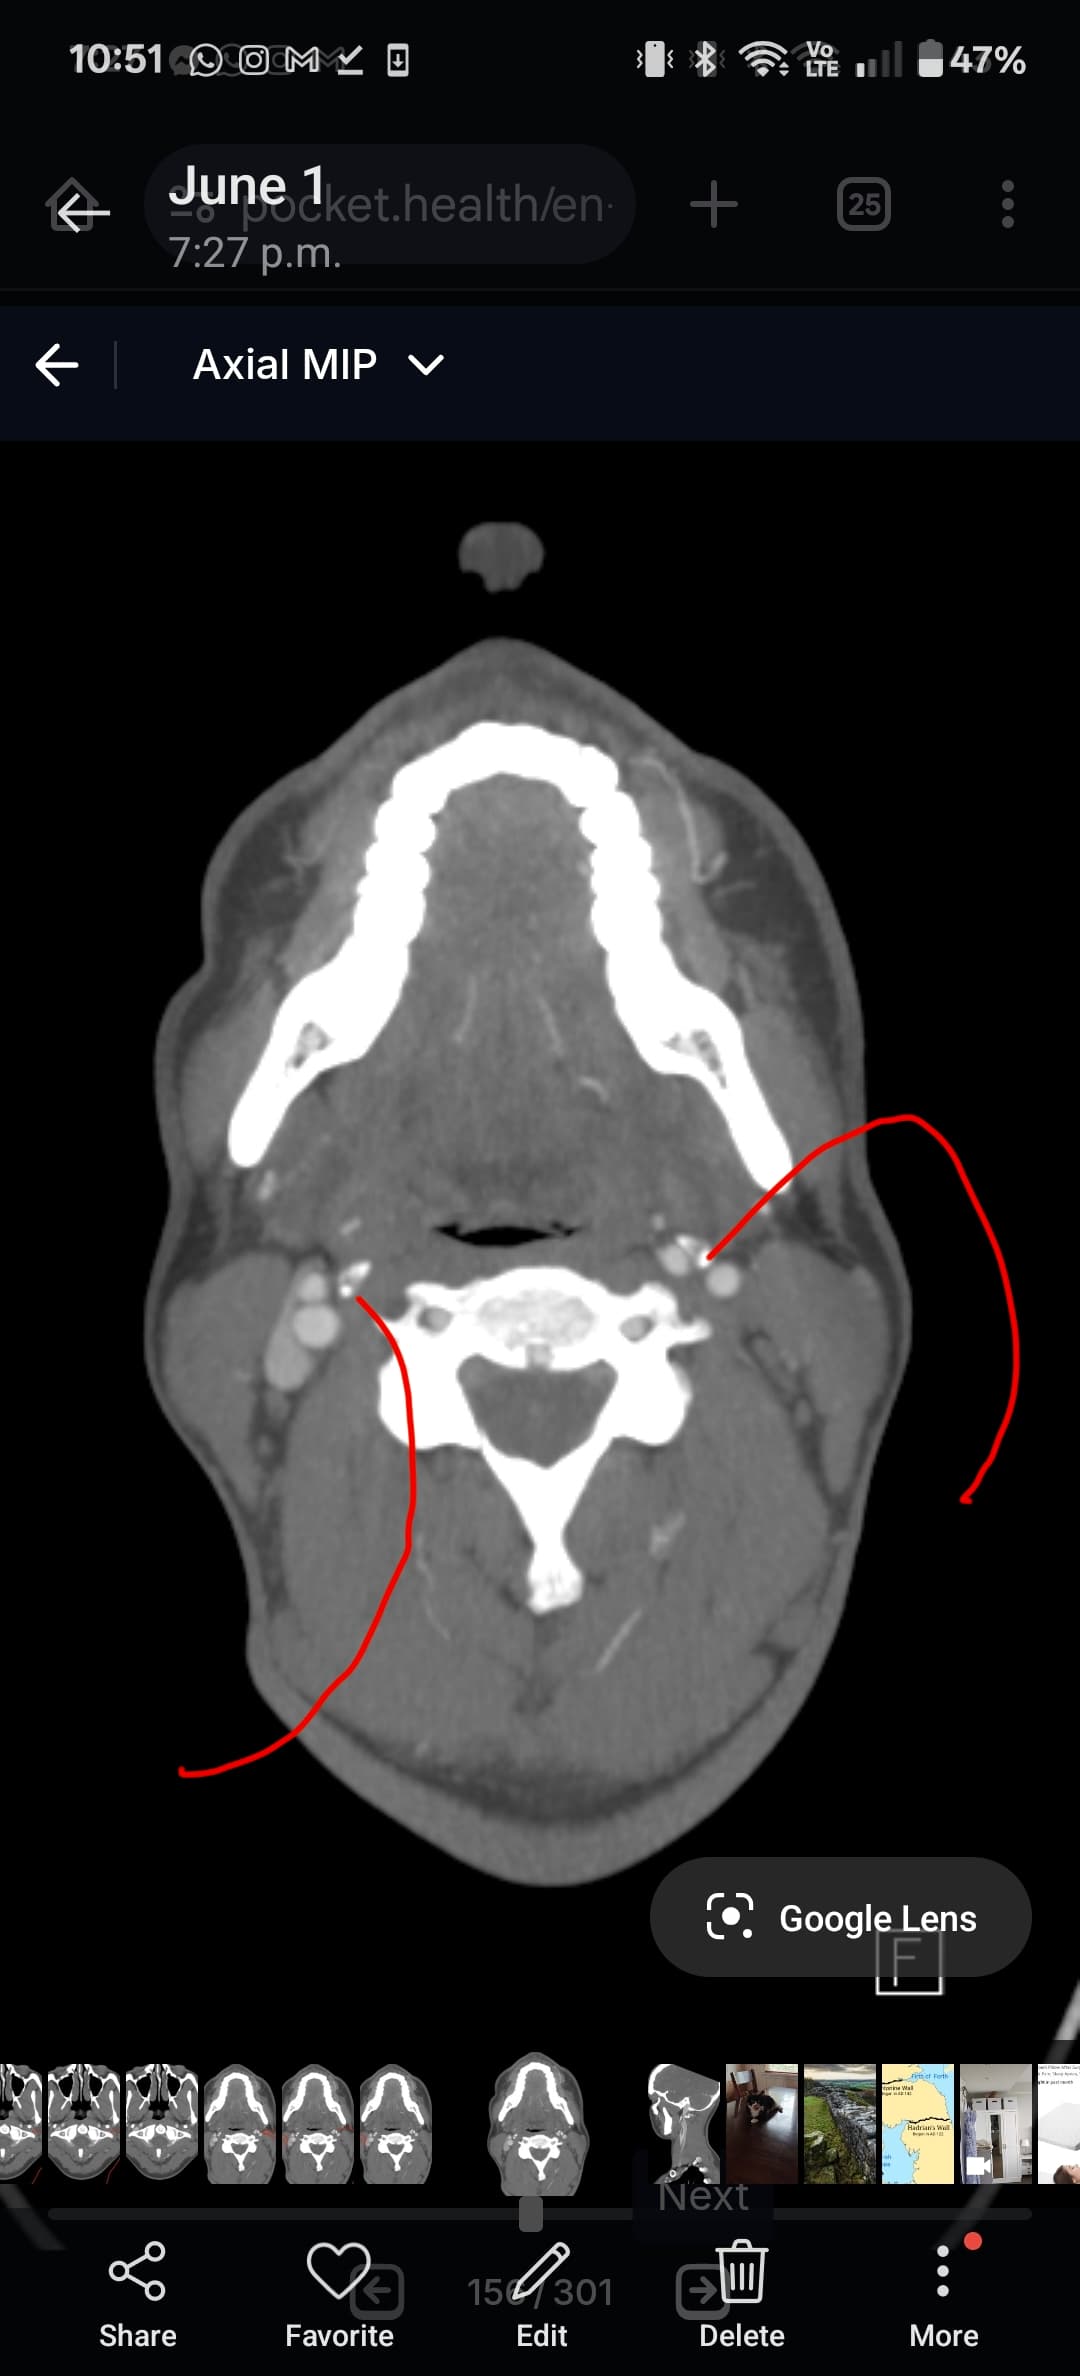

I think the best CT imaging view to look at whether your hyoid is digging into anything is by going into the axial view of your imaging. In the axial view look for the horseshoe shaped hyoid bone. I’ve attached what to look for. Take a couple screen shots and upload them and I can help interpret the imaging.

In your first & last pictures, you can see how close to your spine the greater horns of your hyoid are. Your whole hyoid looks like it’s been pushed back further in your neck than it should be possibly producing Hyoid Bone Syndrome (HBS).

@leo this is the closest one. Can you go back to your axial view and go to the very last slice that you can see the tips? I think you might be one or two frames off. I attached my imaging to help. Our hyoids might be at slightly different angles so it might not be a perfect comparison, but I think you can go up a slice or two to see the tips better. Basically follow the bone until it disappears then go back one frame to capture it.